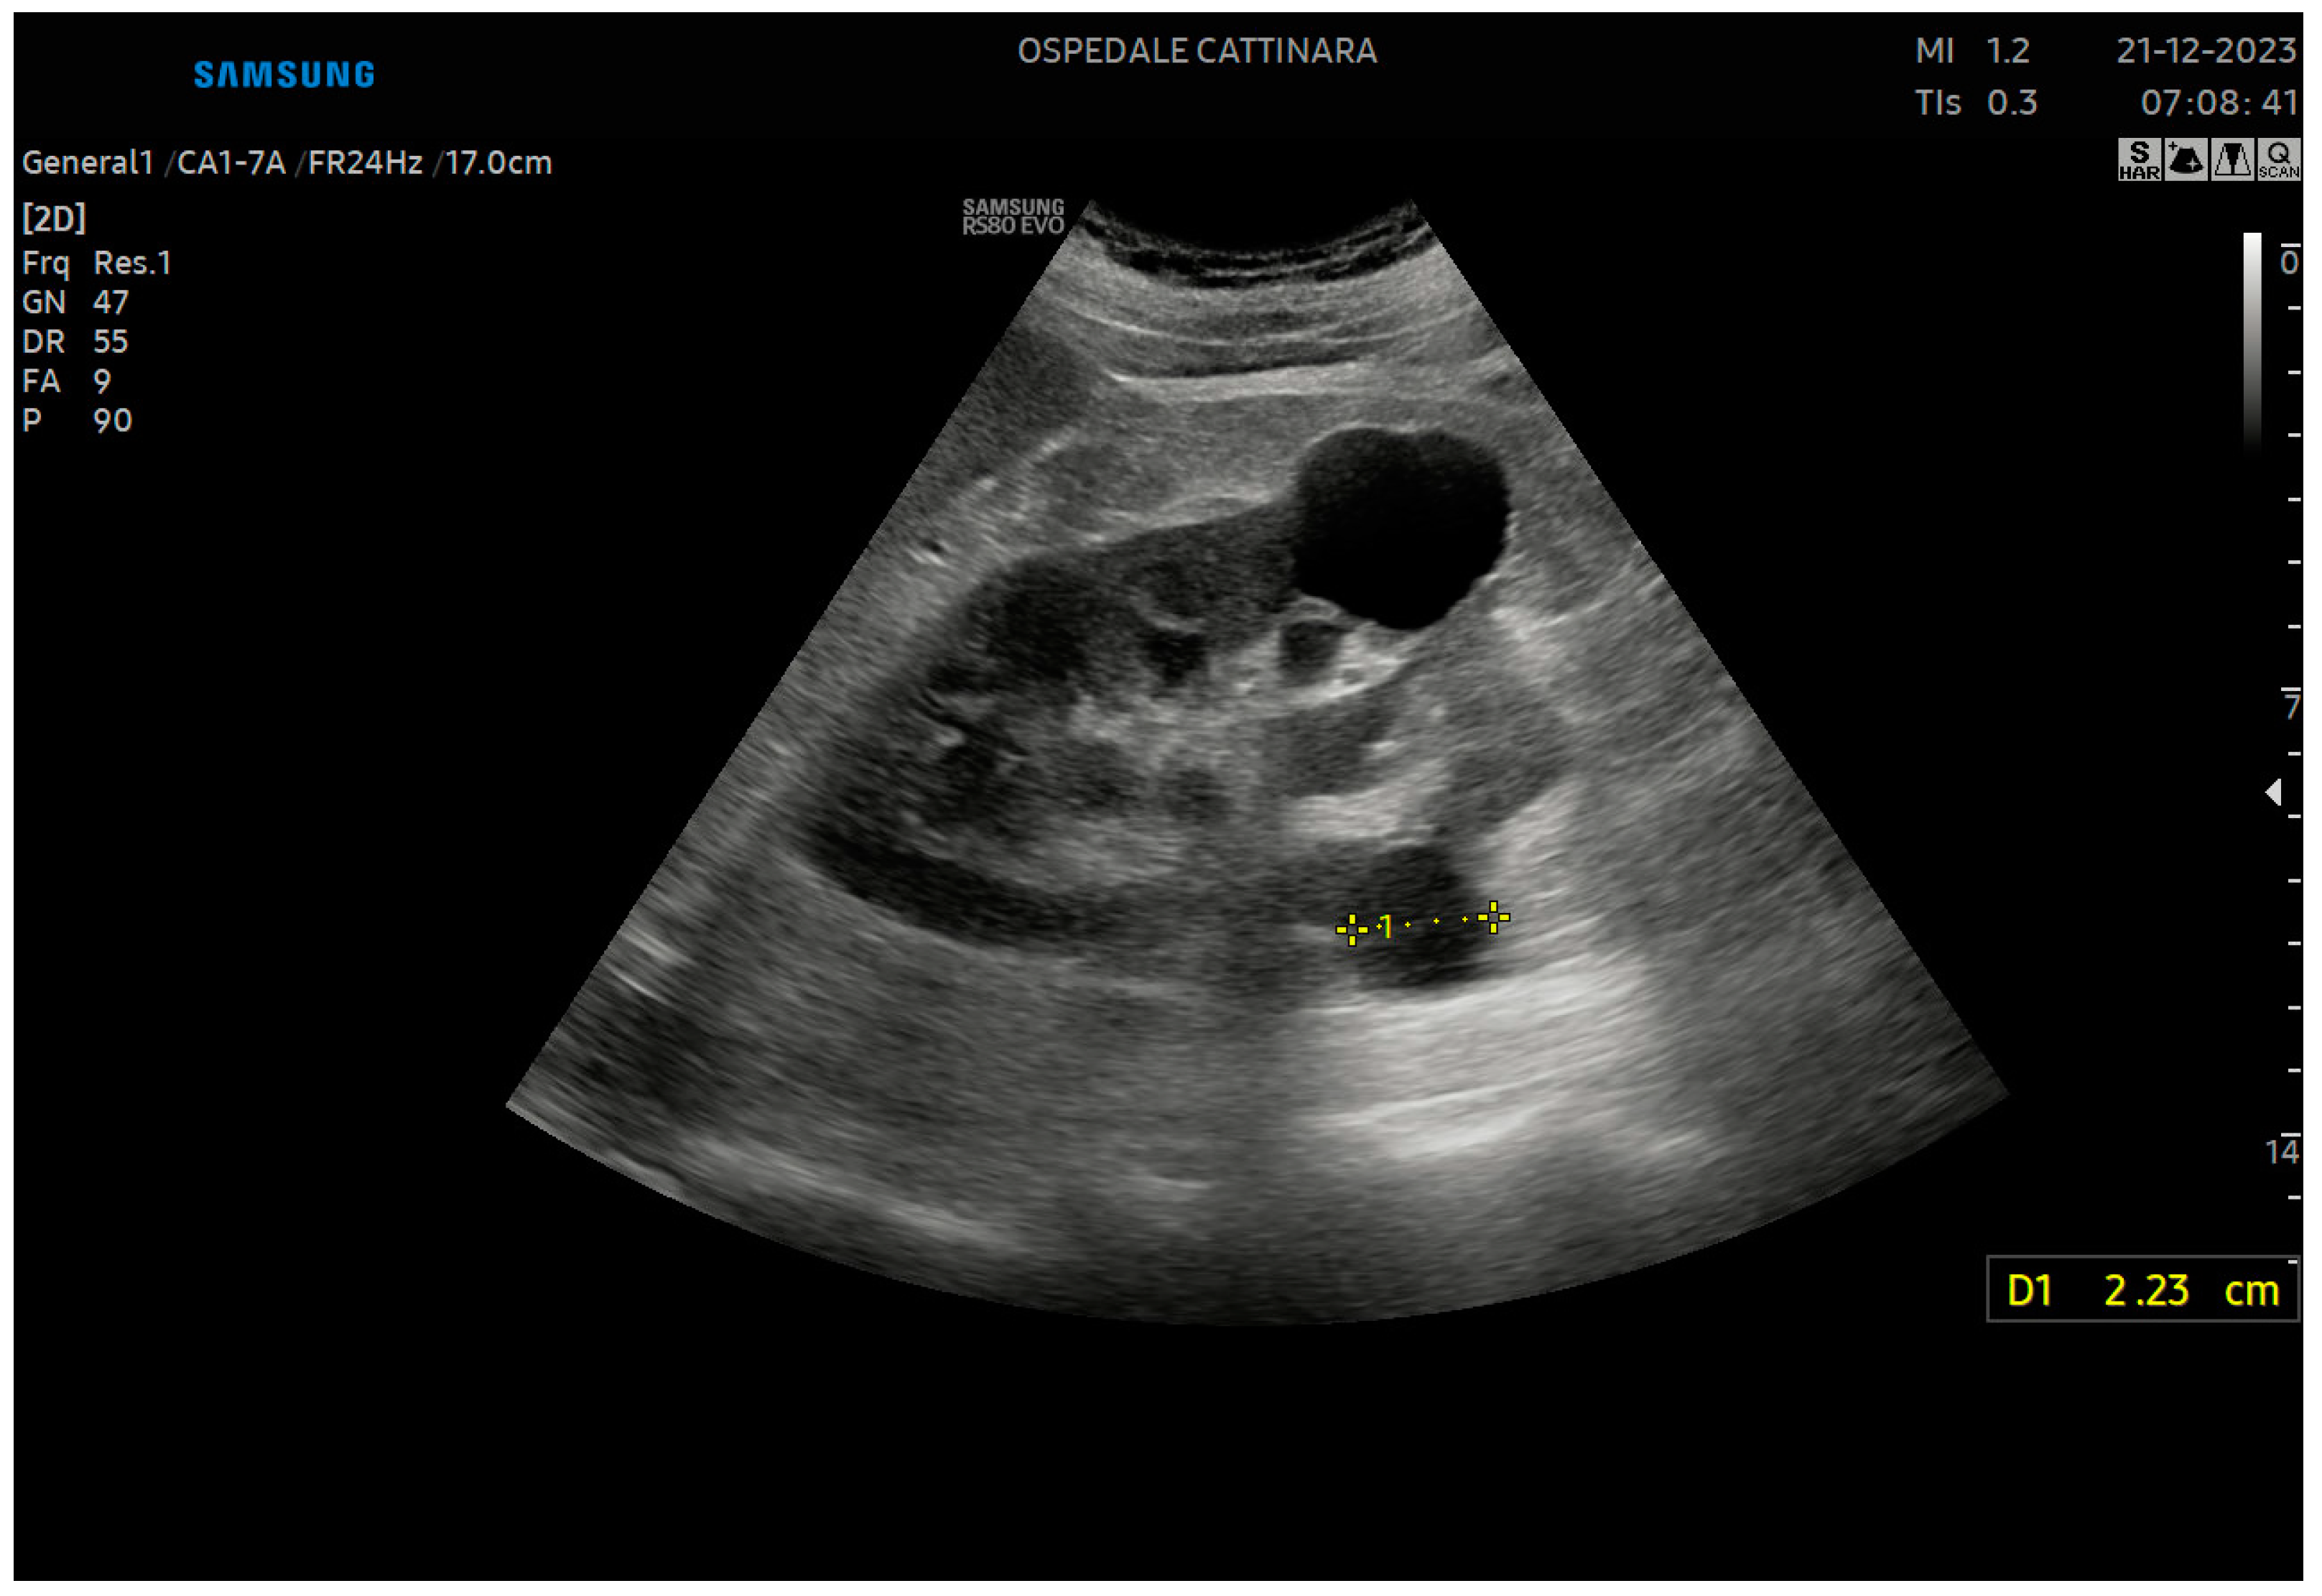

ccr31934-toc-0001-m.jpg?trick=。Frontiers | Urinary Ultrasound and Other Imaging for。Ultrasound of the Urinary System | SpringerLink。【書籍の概要】本書は腎臓超音波検査に特化した図版集であり、医療従事者や学生にとって貴重な参考資料です。視覚的な情報が豊富で、腎臓の解剖や病理を理解するのに役立ちます。【内容の特徴】各章には腎臓に関する詳細な超音波画像とともに、解説が付されています。これにより、実際の診断や研究に役立つ情報が得られます。【対象読者】医療従事者、特に放射線技師や腎臓専門医、または腎臓に関心のある学生に最適です。- 書名: ATLAS OF Renal Ultrasonography- 著者: O'NEILL- 内容: 腎臓超音波検査に関する図版と解説- 表紙の色: 青と赤のグラデーションご覧いただきありがとうございます。。。【 新品未使用 】 最新医学大辞典。宇宙論と神。DVD>松本岐子先生 明日からの臨床に使える鍼灸療法 1巻2巻set。専用⭐︎美品】健康管理士一般指導員 検定書セット 1-6巻。未開封品 DVD 岩橋 亮平 4回リピート制! 産後ママに評判の骨盤矯正